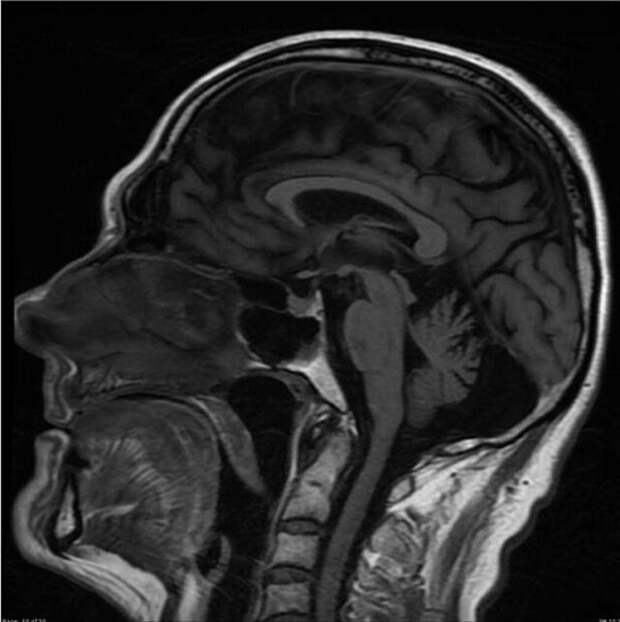

Алкогольная атрофия мозга  МРТ оперного певца

МРТ оперного певца  Зубы в семь лет и в тридцать